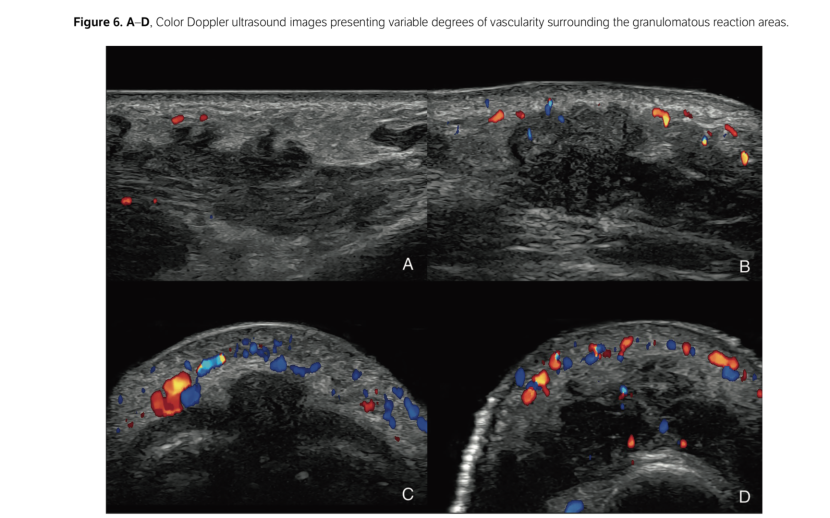

L'incidenza delle complicazioni da filler a base di HA del volto è aumentata significativamente. In questo contesto, l'ecografia, e in particolare l'ecografia Doppler, è diventata uno strumento importante per migliorare la sicurezza dei trattamenti con filler a base di acido ialuronico. L'esame ecografico può aiutare sia nella prevenzione delle complicazioni sia nella loro gestione utilizzando le ialuronidasi in ecoguida. Per avvalorare questo discorso, uno studio molto importante (DELPHI) riguardo l’utilizzo dell’ecografia nelle infiltrazioni del volto, dichiara una forte raccomandazione (obbligo) nell' utilizzo in alcune aree più sensibili ad eventi vascolari.